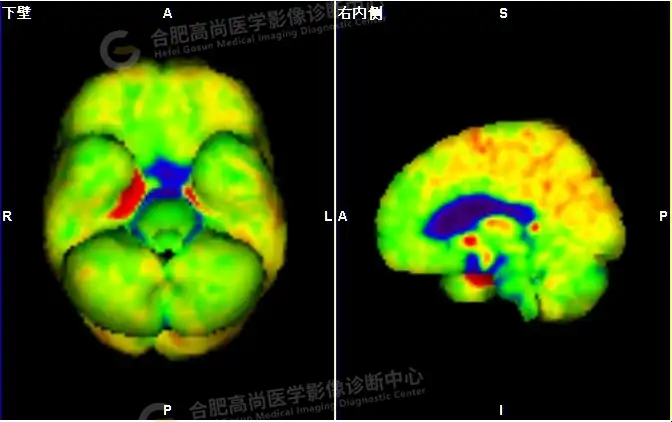

18F -FDG PET/CT检查图像:

18F -FDG PET/CT检查所见:

发作间期显像:PET显像双侧海马呈放射性摄取异常增高,以右侧明显,右侧海马SUVmax16.1、SUVavg4.4,左侧海马SUVmax7.3、SUVavg3.1(同层面额叶脑皮质SUVmax5.9、SUVavg2.3);CT示左侧海马体积较右侧似轻度缩小,左侧侧脑室颞角轻度增宽。PET显像右侧杏仁核及右侧基底节区局灶性放射性摄取异常增高,SUVmax14.1、SUVavg5.7(左侧SUVmax5.1、SUVavg3.6);CT示右侧杏仁核及右侧基底节区大小、形态正常,未见异常密度灶。

18F -FDG PET/CT检查结论:

发作间期显像:双侧海马、及右侧基底节区FDG代谢异常增高,考虑致癫灶可能大,请结合临床。